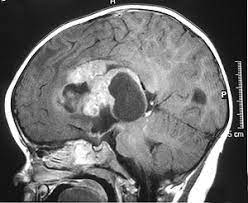

Mri of an atypical teratoid rhabdoid tumor (atrt) in the brain.

Headache, generally upon awakening in the morning hydrocephalus, where there is a buildup of fluid in the brain, can increase head size in infants or headaches and vomiting in older children nausea and vomiting, often worse in the morning and improve throughout the day An atypical teratoid rhabdoid tumor (atrt) is a very rare, aggressive tumor of the central nervous system, occurring mostly in the cerebellum, the part of the brain that controls movement and balance, or the brain stem, the part of the brain that controls basic body functions. Headache, which is often worse in the morning or improves after vomiting Check with your child's doctor if your child has any of the following: The other symptoms depend on where in the body the cancer. What are the signs and symptoms of a pediatric atypical teratoid rhabdoid tumor (atrt)? Occasionally, older children can be diagnosed with at/rt. Declan, then 15 months old, had an atypical teratoid rhabdoid tumor (at/rt), a rare cancer that affects the brain and central nervous system. Signs and symptoms may be caused by atrt or by other conditions. The tumors may arise anywhere in the nervous system but typically appear in the cerebellum. Symptoms of a brain tumor develop when abnormal tissue expands and puts pressure on healthy brain tissue or the tumor interferes with the normal flow of fluid around the brain and spinal cord. To get an accurate diagnosis, a piece of tumor tissue will be removed during surgery, if possible. Background cancer is the second leading cause of death in children, after accidents.